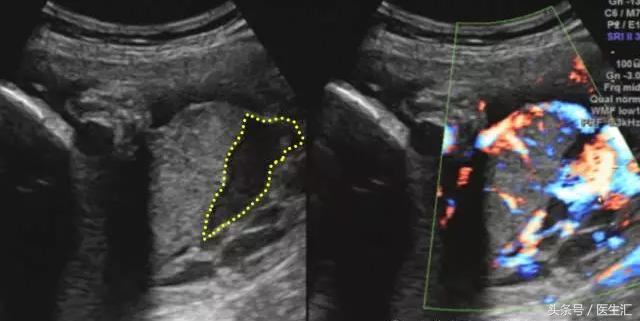

超声检查提示:宫底后壁胎盘与后壁肌层之间见混合回声区(超声表现1,见图1黄色圈内),与胎盘分界不清,范围约75mm×34mm,内回声不均匀,边缘及内部未见明显血流信号(检查要点1)。急诊剖宫产手术见胎盘80mm×50mm剥离面,占1/2(超过胎盘面积的1/3),宫腔积血约50ml,术后诊断胎盘早剥。

(图1)